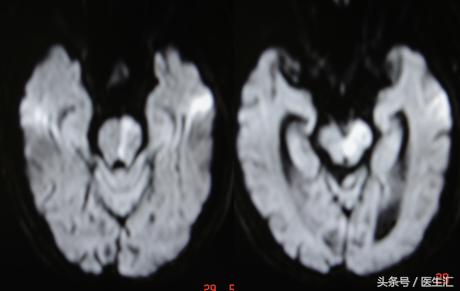

MRI示:左丘脑、左枕叶、小脑蚓部、桥脑急性脑梗塞(见图9)